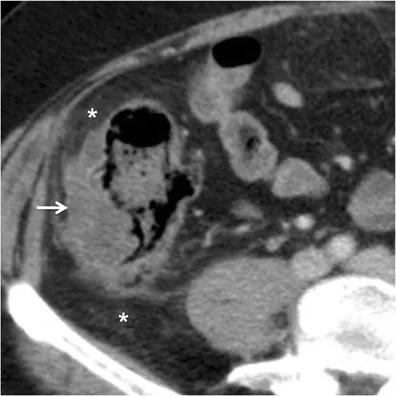

- Abdominal/pelvic CT with contrast is the best initial and most accurate test.

- Key findings: Localized bowel wall thickening (>4 mm), pericolic fat stranding, abscess, or extraluminal air/fluid.